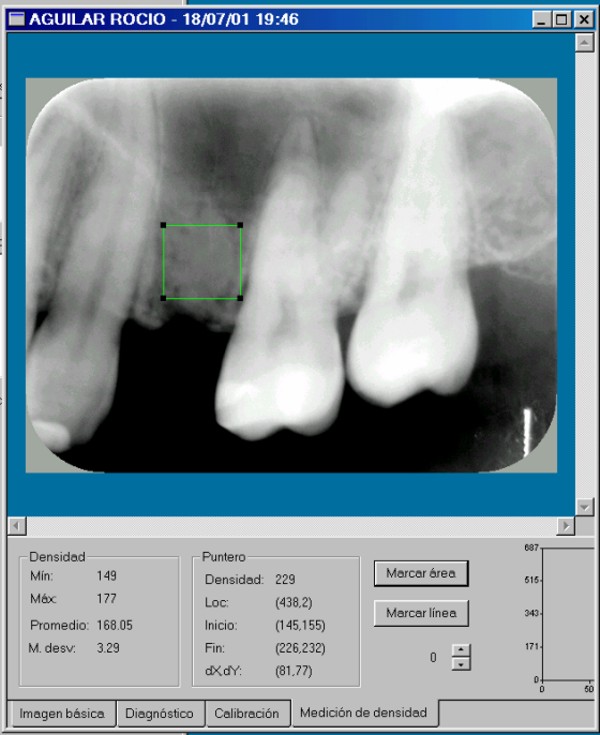

Hubiera sido necesaria la comparación osteodensitométrica entre la zona a implantar y otras zonas maxilares.(DIAPO 8-9-10)

DENSIDAD PROMEDIO:194.87 DENSIDAD PROMEDIO:158.49

DIAPO 8 DIAPO 9

DENSIDAD PROMEDIO:168.5

REF 1